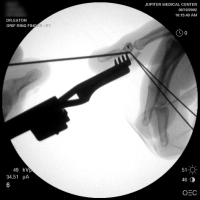

| A midline longitudinal palmar approach was used. This view shows a transverse pin across the dorsal proximal fragment, to be used as a path for interosseous wiring. Additional pins have been placed across each single cortex for later advancement. |

| A wire was passed through the dorsal proximal pin track and then around the palmar pins. After reduction and tightening this wire, the pins were advanced to engage the dorsal cortex. |